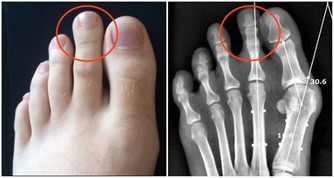

有對長壽的夫妻,丈夫不菸不酒愛運動,是個瘦子,太太則完全相反,是個胖子,兩人同時得到流感,變成肺炎!結果太太幾天就恢復出院,丈夫卻住進加護病房...為甚麼會這樣呢?醫生解釋,因為瘦,膽固醇低,罹患肺炎時,身體沒有儲備能量,容易有併發症。